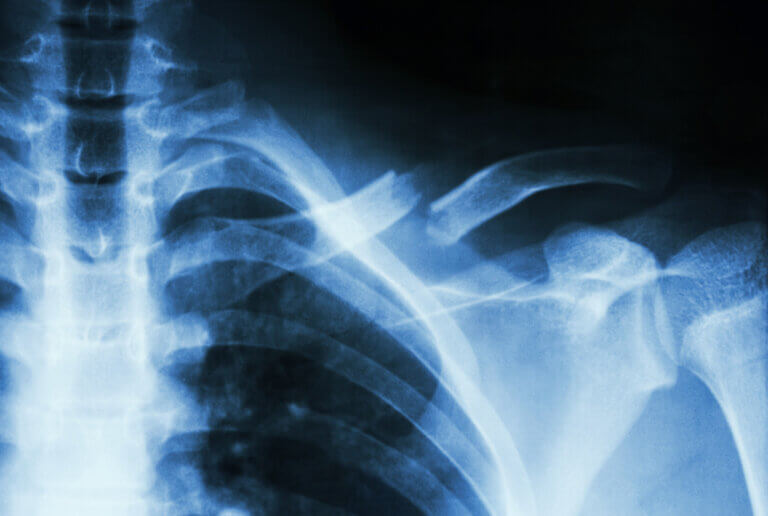

1. Fractura de clavícula

La fractura de clavícula ocurre por un trauma directo sobre el hombro, como puede pasar en accidentes de tránsito o al realizar algún deporte. Suele generar dolor en la clavícula luego del golpe y, en ocasiones, se evidencia deformidad en la zona fracturada.

Para su manejo, se requiere inmovilización del miembro superior con cabestrillo y analgésicos. En algunos casos, donde la lesión se encuentra muy desplazada o hay compromiso neurovascular de la extremidad, se requiere de cirugía.